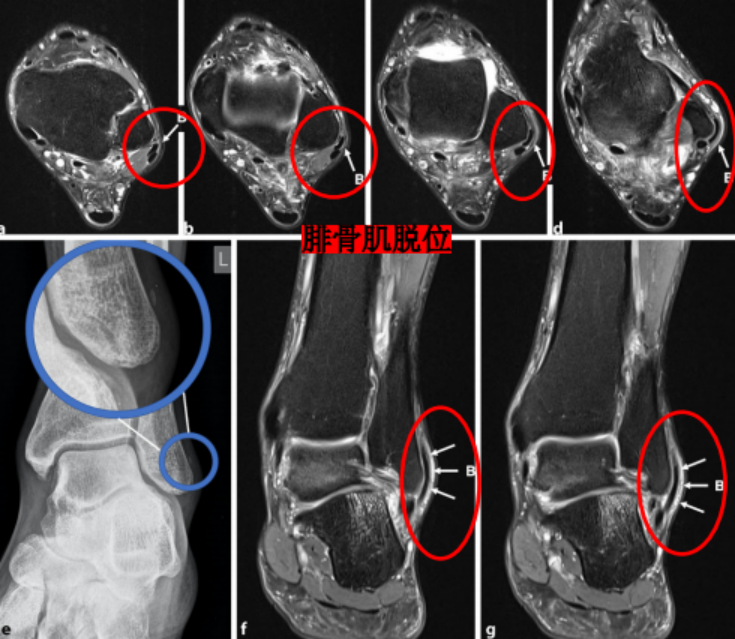

Ecket和Davis根据73例手术患者的术中观察发现并无腓骨上支持带的撕裂,他们将患者分为3型:

I型:最常见(51%),腓骨上支持带(SPR)和骨膜仍保持联系,骨膜从外踝上撕脱,腓骨肌腱滑向前方使骨膜和外踝分离。

Ⅱ型:(33%)纤维软骨脊连同腓骨上支持带(SPR)一起和外踝分离,腓骨肌腱向前脱位。

Ⅲ型:(16%)纤维软骨脊连同部分外踝骨质和腓骨上支持带(SPR)一起与外踝分离,肌腱脱位至骨折块下方。

IV型:Oden1987年在此基础上外,还有少见的第IV型,表现为腓骨上支持带(SPR)的完全撕脱或断裂,并且肌腱移位于支持带的外表面。

I型损伤只能在手术中分型,只有在脱位时才不稳定;Ⅱ型损伤只能在手术中分型,复位后也不稳定;Ⅲ型损伤可以通过放射平片检查发现,复位后非常不稳定。

X线检查:腓骨肌腱脱位伴腓骨撕脱骨折(斑点征)有一定的诊断意义。

CT∶可显示腓骨外侧窝的解剖形态、腓骨撕脱骨折及腓骨肌腱的位置。

MRI:能更清楚地显示软组织损伤情况,如支持带撕裂和腓骨肌腱半脱位。对于指导临床治疗及后期随访观察疗效具有重要参考价值。